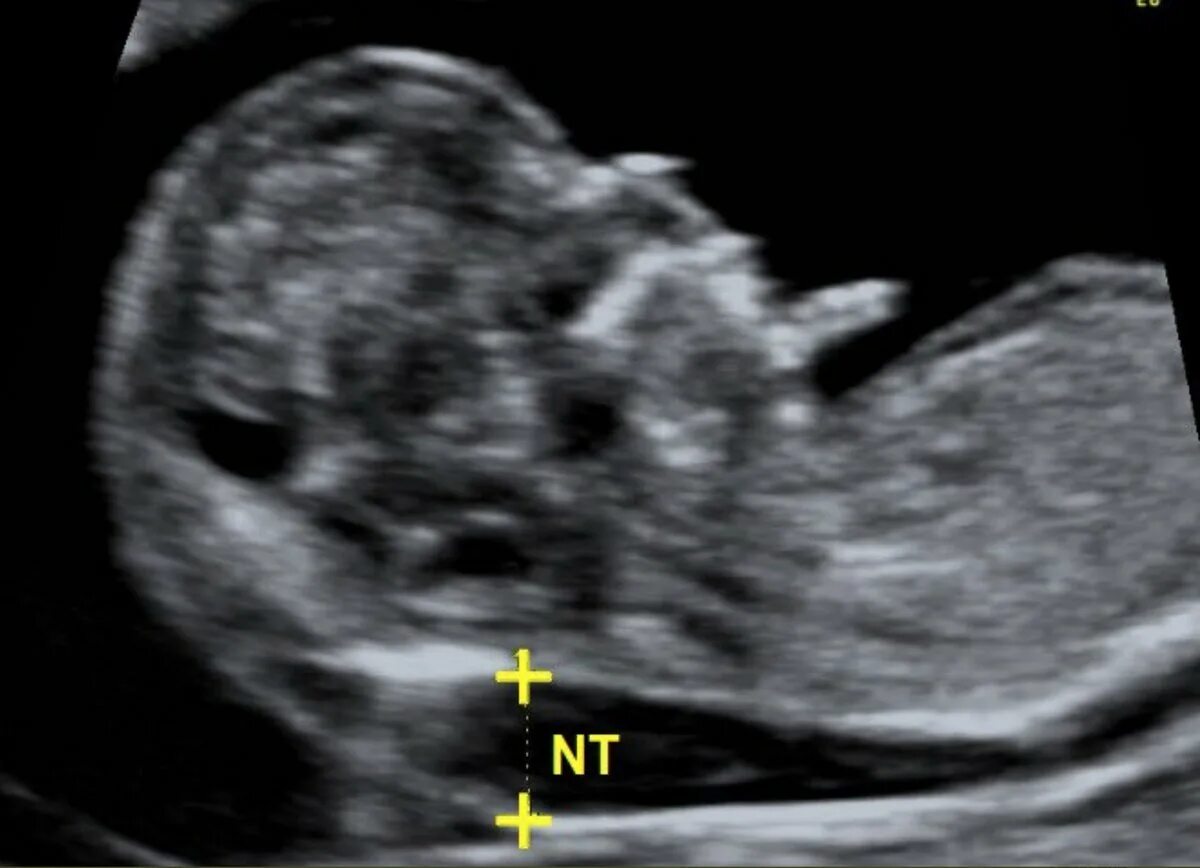

Воротниковое пространство 5